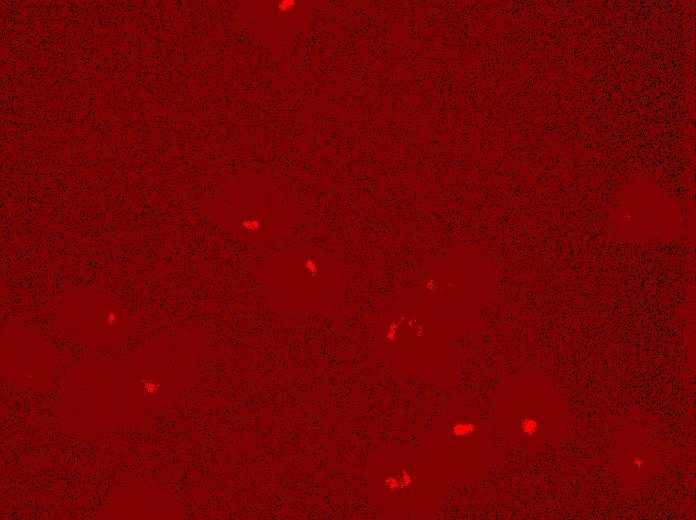

SMAD4